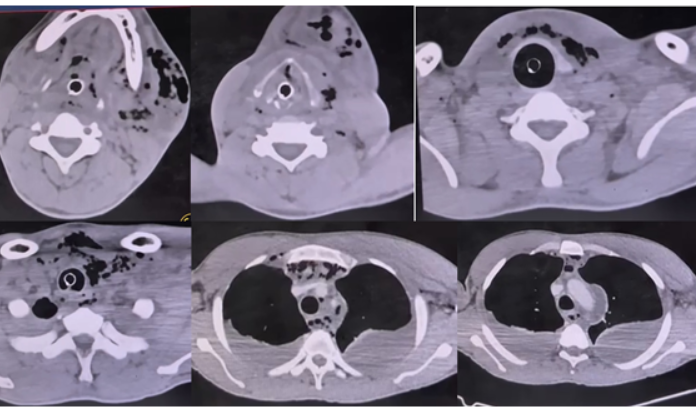

11

Q

abscesso cervical e mediastinite